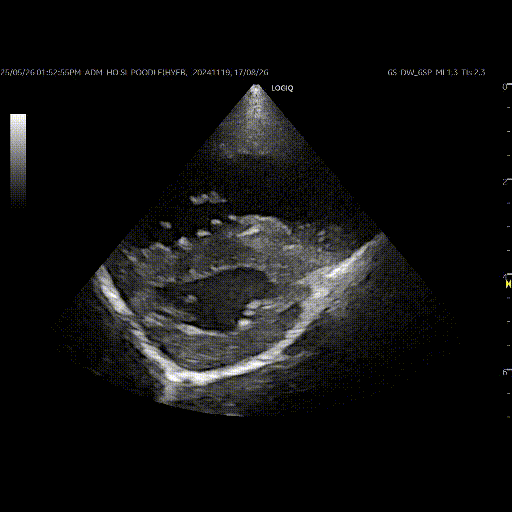

폐동맥 고혈압은 주로 엑스레이, 심장 초음파 검사 등 영상검사를 통해 평가하게 됩니다.

엑스레이 상의 기관지, 폐 실질 등 폐에 대한 평가와 더불어 심장의 외관상의 크기 형태 등의 평가를 병행하게 됩니다. 앞서 언급을 드린 것처럼 폐동맥 고혈압은 폐 질환에 이차적인 경우가 많기 때문에 엑스레이를 통한 폐의 기능을 평가하는 것이 중요합니다. 그 외에도 폐동맥 고혈압의 원인이 될수 있는 심장사상충에 대한 키트 검사도 병행하게 됩니다.

폐동맥 고혈압의 정도와 단계에 대한 평가는 주로 심장 초음파 검사를 진행합니다.

폐동맥에서 우심실 쪽으로 발생하는 역류 여부, 우심실에서 우심방으로 역류되는 혈류 등의 평가를 통해 폐동맥 고혈압의 단계를 추정하게 됩니다.